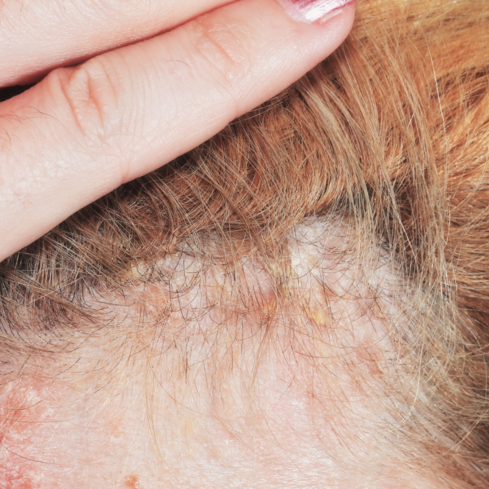

Na postižených místech se tyto buňky reprodukují za neuvěřitelných 3 až 6 dní, přičemž standardně tento proces trvá 28 dní. Výsledkem je vznik silných, zarudlých a šupinatých ložisek – lupénky.